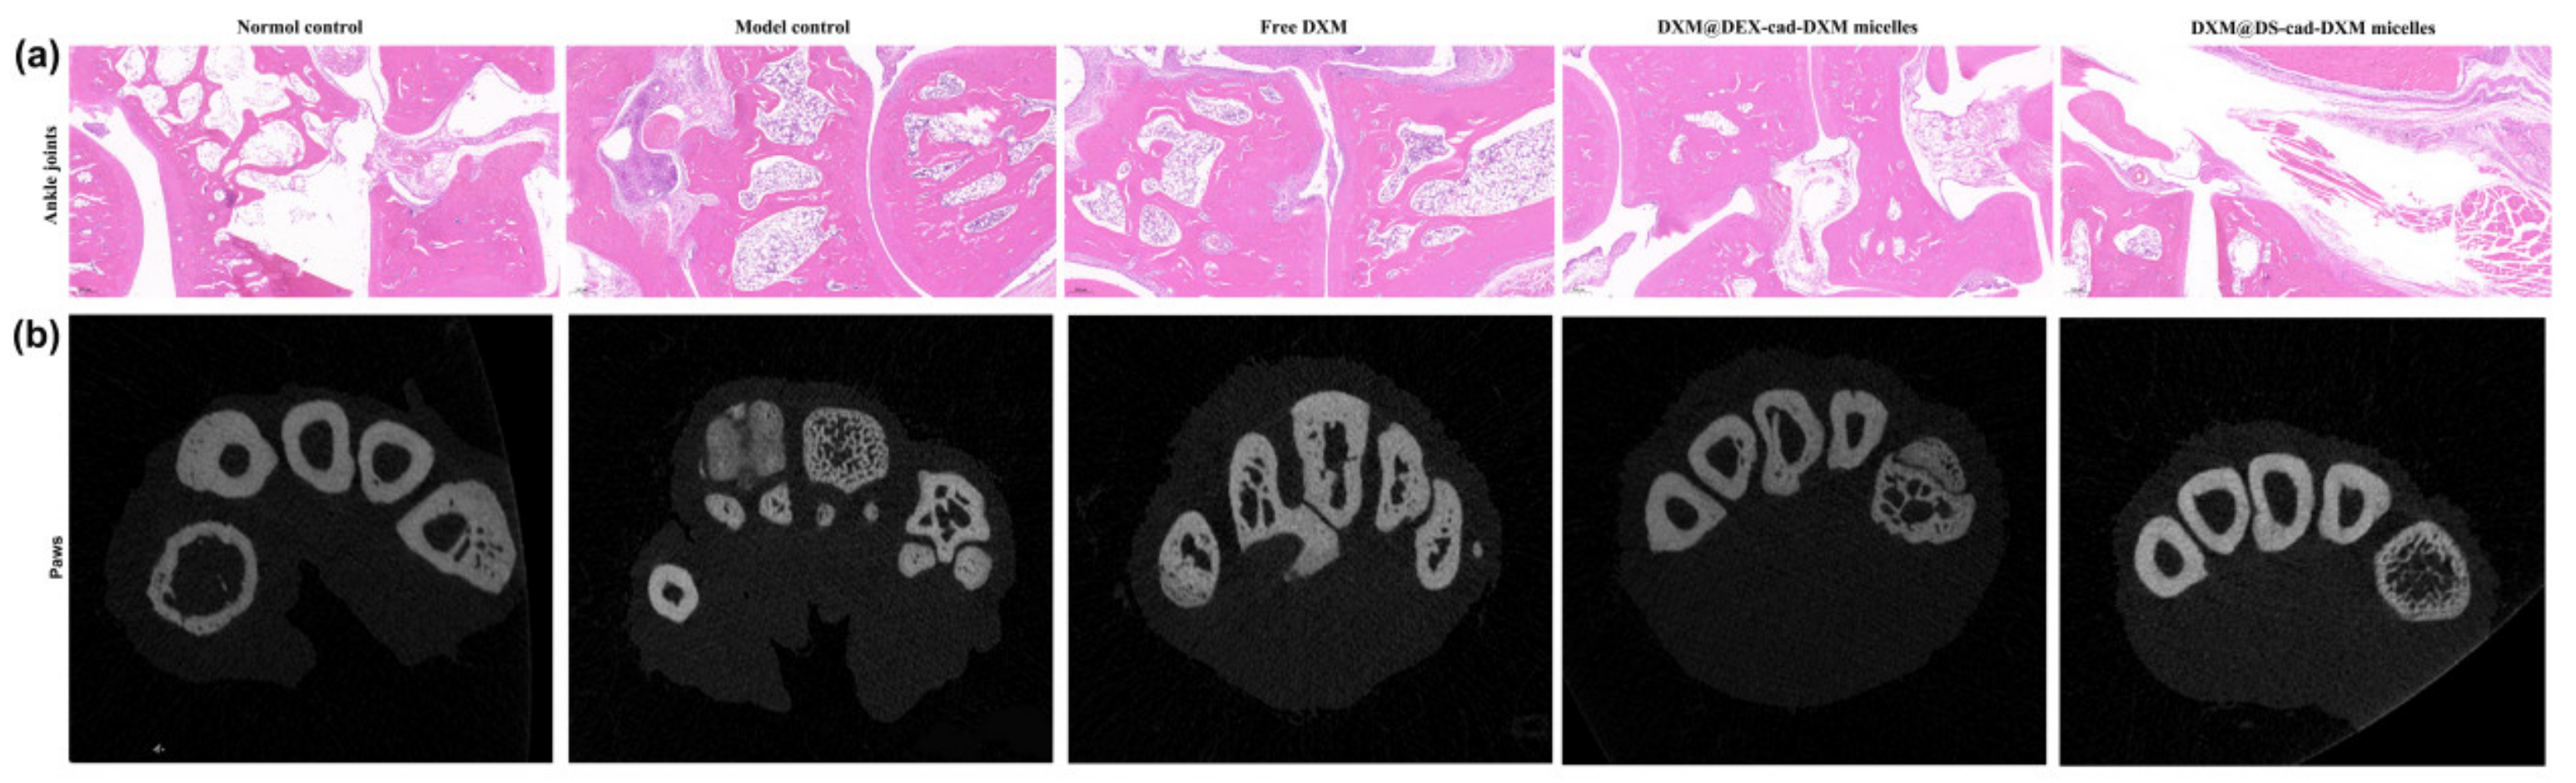

Hematoxylin–eosin was performed to evaluate the histological changes in ankle joints after treatments. As shown in Figure 8a, in the model control rats, the joint cavity was narrowed due to the excessive proliferation of inflammatory cells, and significant erosion of cartilage was present. The treatment of free DXM alleviated the inflammatory infiltrate slightly, but tissue damage was still evident. DXM@DEX-cad-DXM micelles showed strong anti-inflammatory activity, yet obvious synovial hyperplasia and mild articular cartilage erosion can still be observed. In contrast, the inflamed joints in AIA rats treated with DXM@DS-cad-DXM micelles showed almost normal articular cavities with no cartilage erosion and mild inflammatory hyperplasia. The Micro-CT was conducted to investigate the structure of inflamed paws in AIA rats after treatments. As shown in Figure 8b, the number of bone trabeculae and bone mineral density in the model control group was obviously decreased, suggesting serious bone destruction in AIA rats. After treatment with DXM@DS-cad-DXM micelles, the number of bone trabeculae and bone mineral density of AIA model rats were significantly increased. In contrast, both free DXM and DXM@DEX-cad-DXM micelles could not remarkably improve the impaired bone quality in the AIA model rats. These results suggested that DXM@DS-cad-DXM micelles have an inhibitory effect on bone destruction caused by inflammation, which was consistent with the above HE results.

Figure 8.

HE staining (a) and micro-CT images (b) of the inflamed joints from AIA rats after being treated with DXM@DS-cad-DXM micelles and DXM@DEX-cad-DXM micelles. Black arrows indicate pannus formation; green arrows indicate bone destruction. Scale bar = 200 μm.